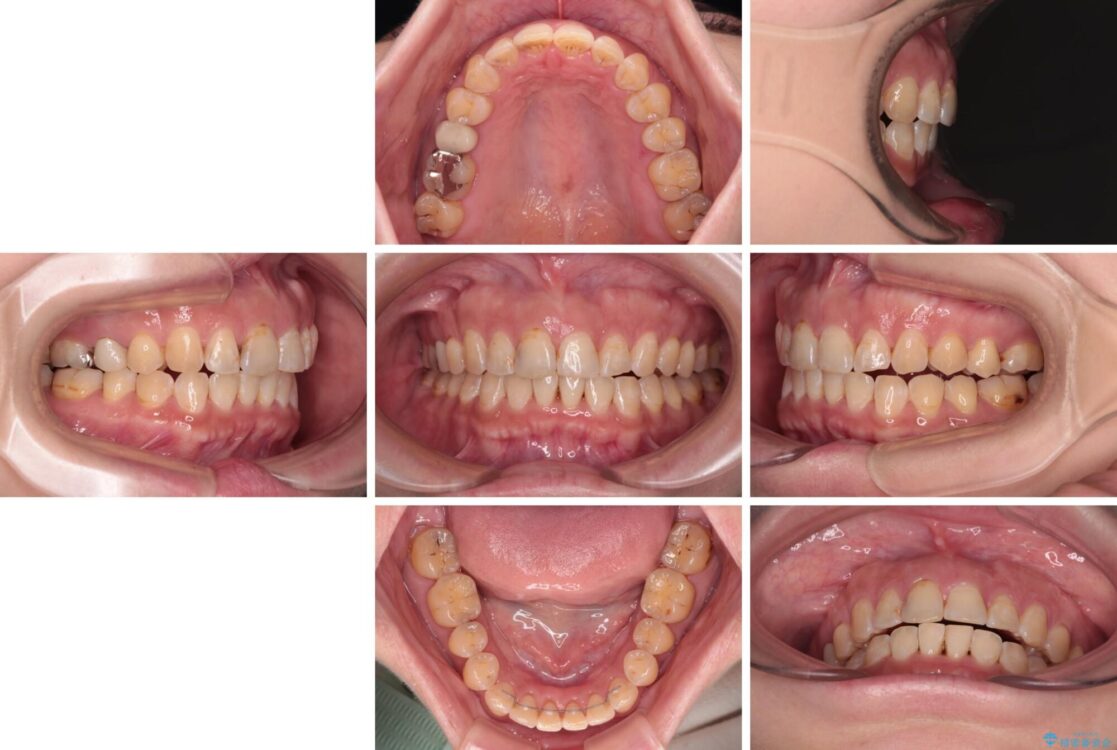

飛び出た上の前歯を気にして来院された患者様です。

奥歯の咬み合わせは、上顎歯列が理想的な一よりも数mm前方にある状態でした。

なるべく早めに治療を終えたいとのことで、補助装置を用いて上顎臼歯を後方に移動させ、同時にワイヤー装置にて整えることとしました。

治療後について

舌の突出癖が原因で上下の歯に大きなスペースが生じていたため、舌のトレーニングをしっかり行っていただくことで、上顎歯列をスムーズに移動させることができました。

治療後

• 【モニター】飛び出た前歯を整えたい ワイヤー矯正治療 治療後画像